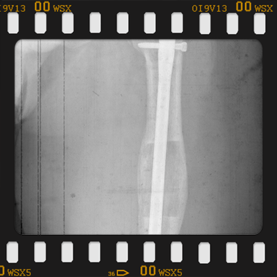

Görüntüleri büyütmek için üzerine tıklayınız.

Görseli büyütmek için üzerine tıklayınız. Görseli büyütmek için üzerine tıklayınız. Radyografi görseli büyütmek için üzerine tıklayınız. Radyografi görseli büyütmek için üzerine tıklayınız. Radyografi görseli büyütmek için üzerine tıklayınız.